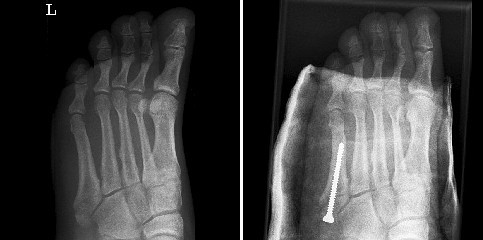

»Die Sehne ist immer stärker als der Knochen«, erklärt der Chirurg seinem Assistenten am Monitor mit der Röntgenaufnahme meines Fußes, »sie hat ihn daher beim Umknicken an der Basis zerrissen.« Es ist so einfach: Sie machen einen kleinen Schnitt an der Seite, drehen eine Schraube hinein und pressen damit die Fragmente so weit aneinander, dass sie wieder vollständig zusammenwachsen können. Wenn sie es nicht täten, erklärt mir der Arzt, wenn sie den Fuß nur in Gips einschlössen, würde der ständige Zug der Sehne dafür sorgen, dass der Knochen nicht verheilt, sondern eine Pseudarthrose entsteht, die dauerhaft Schmerzen verursacht.

vorher — nachher